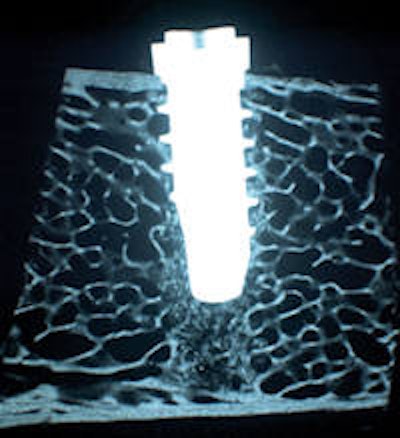

Microradiographic image of SurfLink Dental-treated implant at two weeks after placement in sheep. The implant is closely in contact with both cortical and cancellous bone. Image courtesy of NBMolecules.

To date, the company's clinical data have come from testing SurfLink-coated implants in "small and large animals and now into humans," Aronsson noted. Several self-published white papers have been posted on the company's website. In one white paper, NBMolecules stated that "histological and radiographic evidence clearly showed, even by two weeks, that SurfLink Dental treatment prompted early bone formation on and around the implant surface. And, at 52 weeks, SurfLink Dental-treated implants showed a considerably greater bone-to-implant contact."